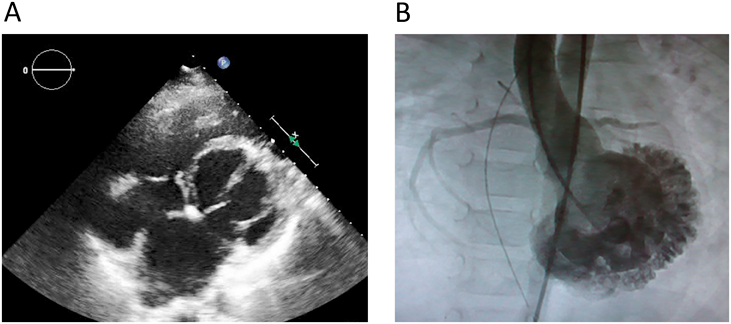

Fig. 2 BiVAD management of 3-years old pure RCM patient

(A) The image of cannulation of EXCOR Pediatric BiVAD. (B) Chest X-ray image when the patient suffered from pulmonary congestion with BiVAD. BiVAD, biventricular assist device; LVAD, left ventricular assist device; RCM, restrictive cardiomyopathy; RVAD, right ventricular assist device.

Fig. 4 Representative images of the patient of left ventricular apical hypoplasia with restrictive physiology

(A) The echocardiographic image. (B) The angiographic image. Note the both images showing lack of left ventricular apex and abnormal trabeculation of left ventricle.